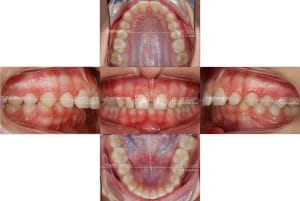

Paciente de 13 años con apiñamiento importante y unas encías muy delicadas, clase II en el lado derecho de la paciente, sobremordida aumentada. Fue tratada durante 14 meses con brackets convencionales.

Después de estudiar bien el caso he decidido junto con la paciente que la mejor opción es extraer un incisivo inferior y así generar espacio suficiente para alinear a todos los dientes y no perjudicar la encía o incluso mejorar el estado de las encías en la parte anterior de abajo. Si en este caso no se hubiera hecho una extracción los más probable es que habría terminado con recesiones gingivales en los caninos (colmillos).

Se colocaron brackets convencionales y se hizo la extracción de un incisivo inferior.